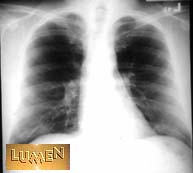

Which X-ray was taken A-P?

Notice the heart size.